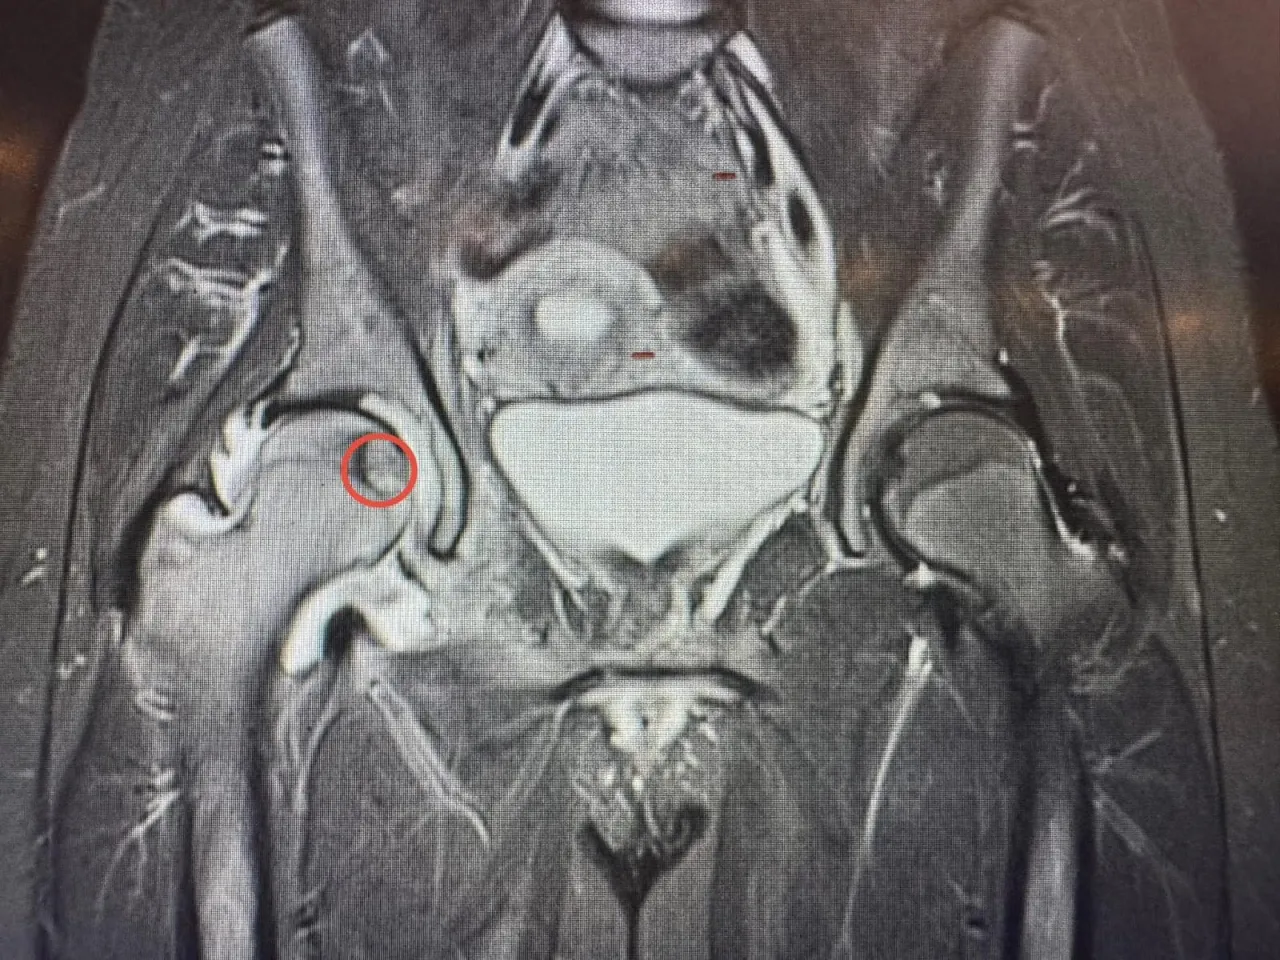

خبرني - أجرى مستشفى الجامعة الأردنيّة، مؤخّرًا، تدخلًا علاجيًّا متقدّمًا في قسم الأشعة، استطاع من خلاله فريقٌ طبيٌّ متعدد الاختصاصات معالجة ورمٍ عظميّ في موقعٍ شديد الحساسيّة داخل رأس عظم الفخذ لمريضٍ ثلاثينيّ، ويُعد هذا الموقع من أكثر المواضع صعوبةً في الوصول إليها جراحيًّا، ما يجعل الخيارات التقليديّة محدودة ويزيد من تعقيد التعامل مع الحالة، لاسيما وأنّ المريض كان يُعاني من آلام حادّة أثّرت بشكل كبير على قدرته على الحركة وممارسة أنشطته اليوميّة.

وبيّن البطوش، أنّ الفريق الطبي نجح في الوصول إلى مركز الورم بدقة عالية باستخدام تقنيّة التصوير الطبقيّ المحوريّ (CT Scan)، تلا ذلك إجراء الكي بالتقنيّة الحراريّة باستخدام المايكروويف (Microwave Ablation)، وهي من أحدث التقنيّات العالميّة في علاج أورام العظام دون الحاجة إلى التدخّل الجراحيّ المفتوح.